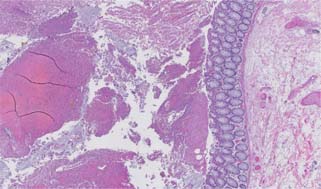

Figure 2: Low power image of colonic mucosa with fibrinopurulent exudate and crystals (Hematoxylin and eosin, 2× magnification).

Figure 3: Medium power image of colonic mucosa with fibrinopurulent exudate and crystals (Hematoxylin and eosin, 5× magnification).